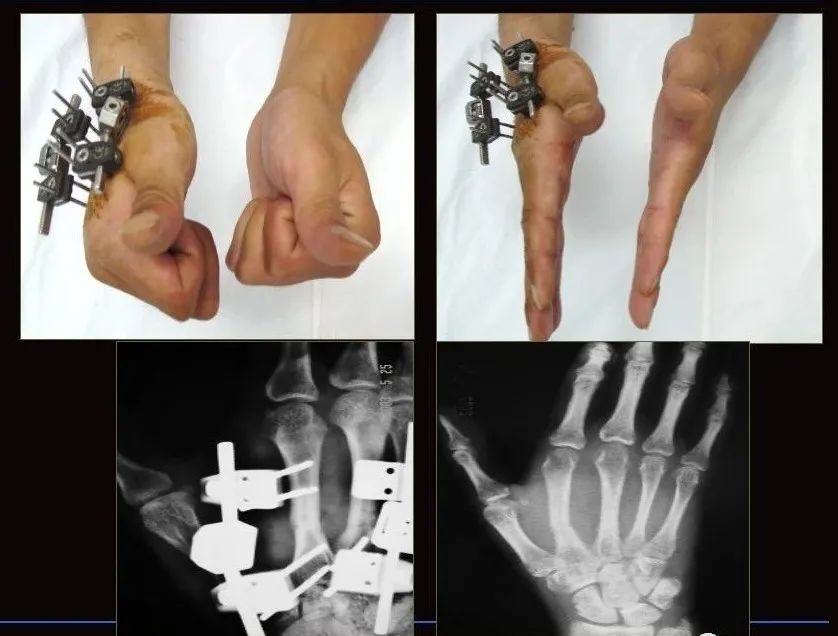

粉碎性掌指骨骨折由于骨支架被破坏,有时手术切开也难以解剖复位或无法坚强内固定。外固定支架使粉碎性骨折在牵引的作用下可恢复并维持其长度,起到相对固定的作用。

不同的掌指骨外固定支架放置部位不同:第1、2掌指骨放置于桡背侧,第4、5掌指骨放置于尺背侧,第3掌指骨则根据情况适当放置于桡背侧或尺背侧,注意进针点以防损伤肌腱。闭合性骨折可在X线下进行闭合复位,复位不理想时可行小切口切开辅助复位。

可有效复位及固定掌指骨关节内骨折而不损伤关节面,并能牵开关节面,防止关节囊和侧副韧带挛缩;

对粉碎性骨折无法解剖复位时,可以结合有限内固定,外固定支架可部分复位并维持力线;

允许未固定关节早期进行患指的功能练习,避免关节僵硬和骨质疏松;

可以有效地固定手部骨折,不影响对患手伤口的术后处理。